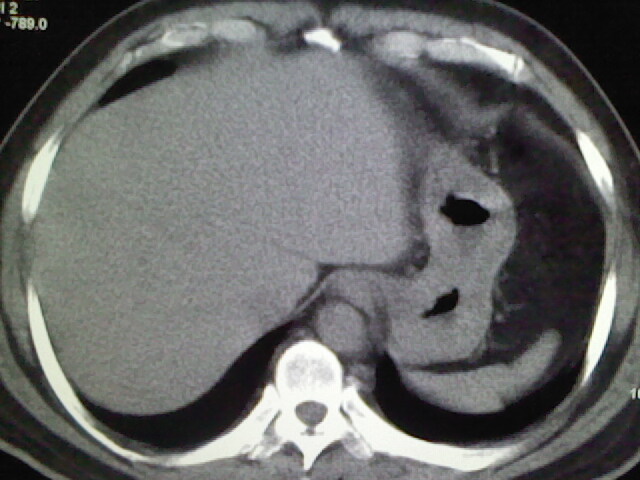

标题: CT17932:临床怀疑肺栓塞

男,34岁,自觉右侧胸痹,胸闷3天余

肺纹理分布较均匀,暂不提示肺梗塞